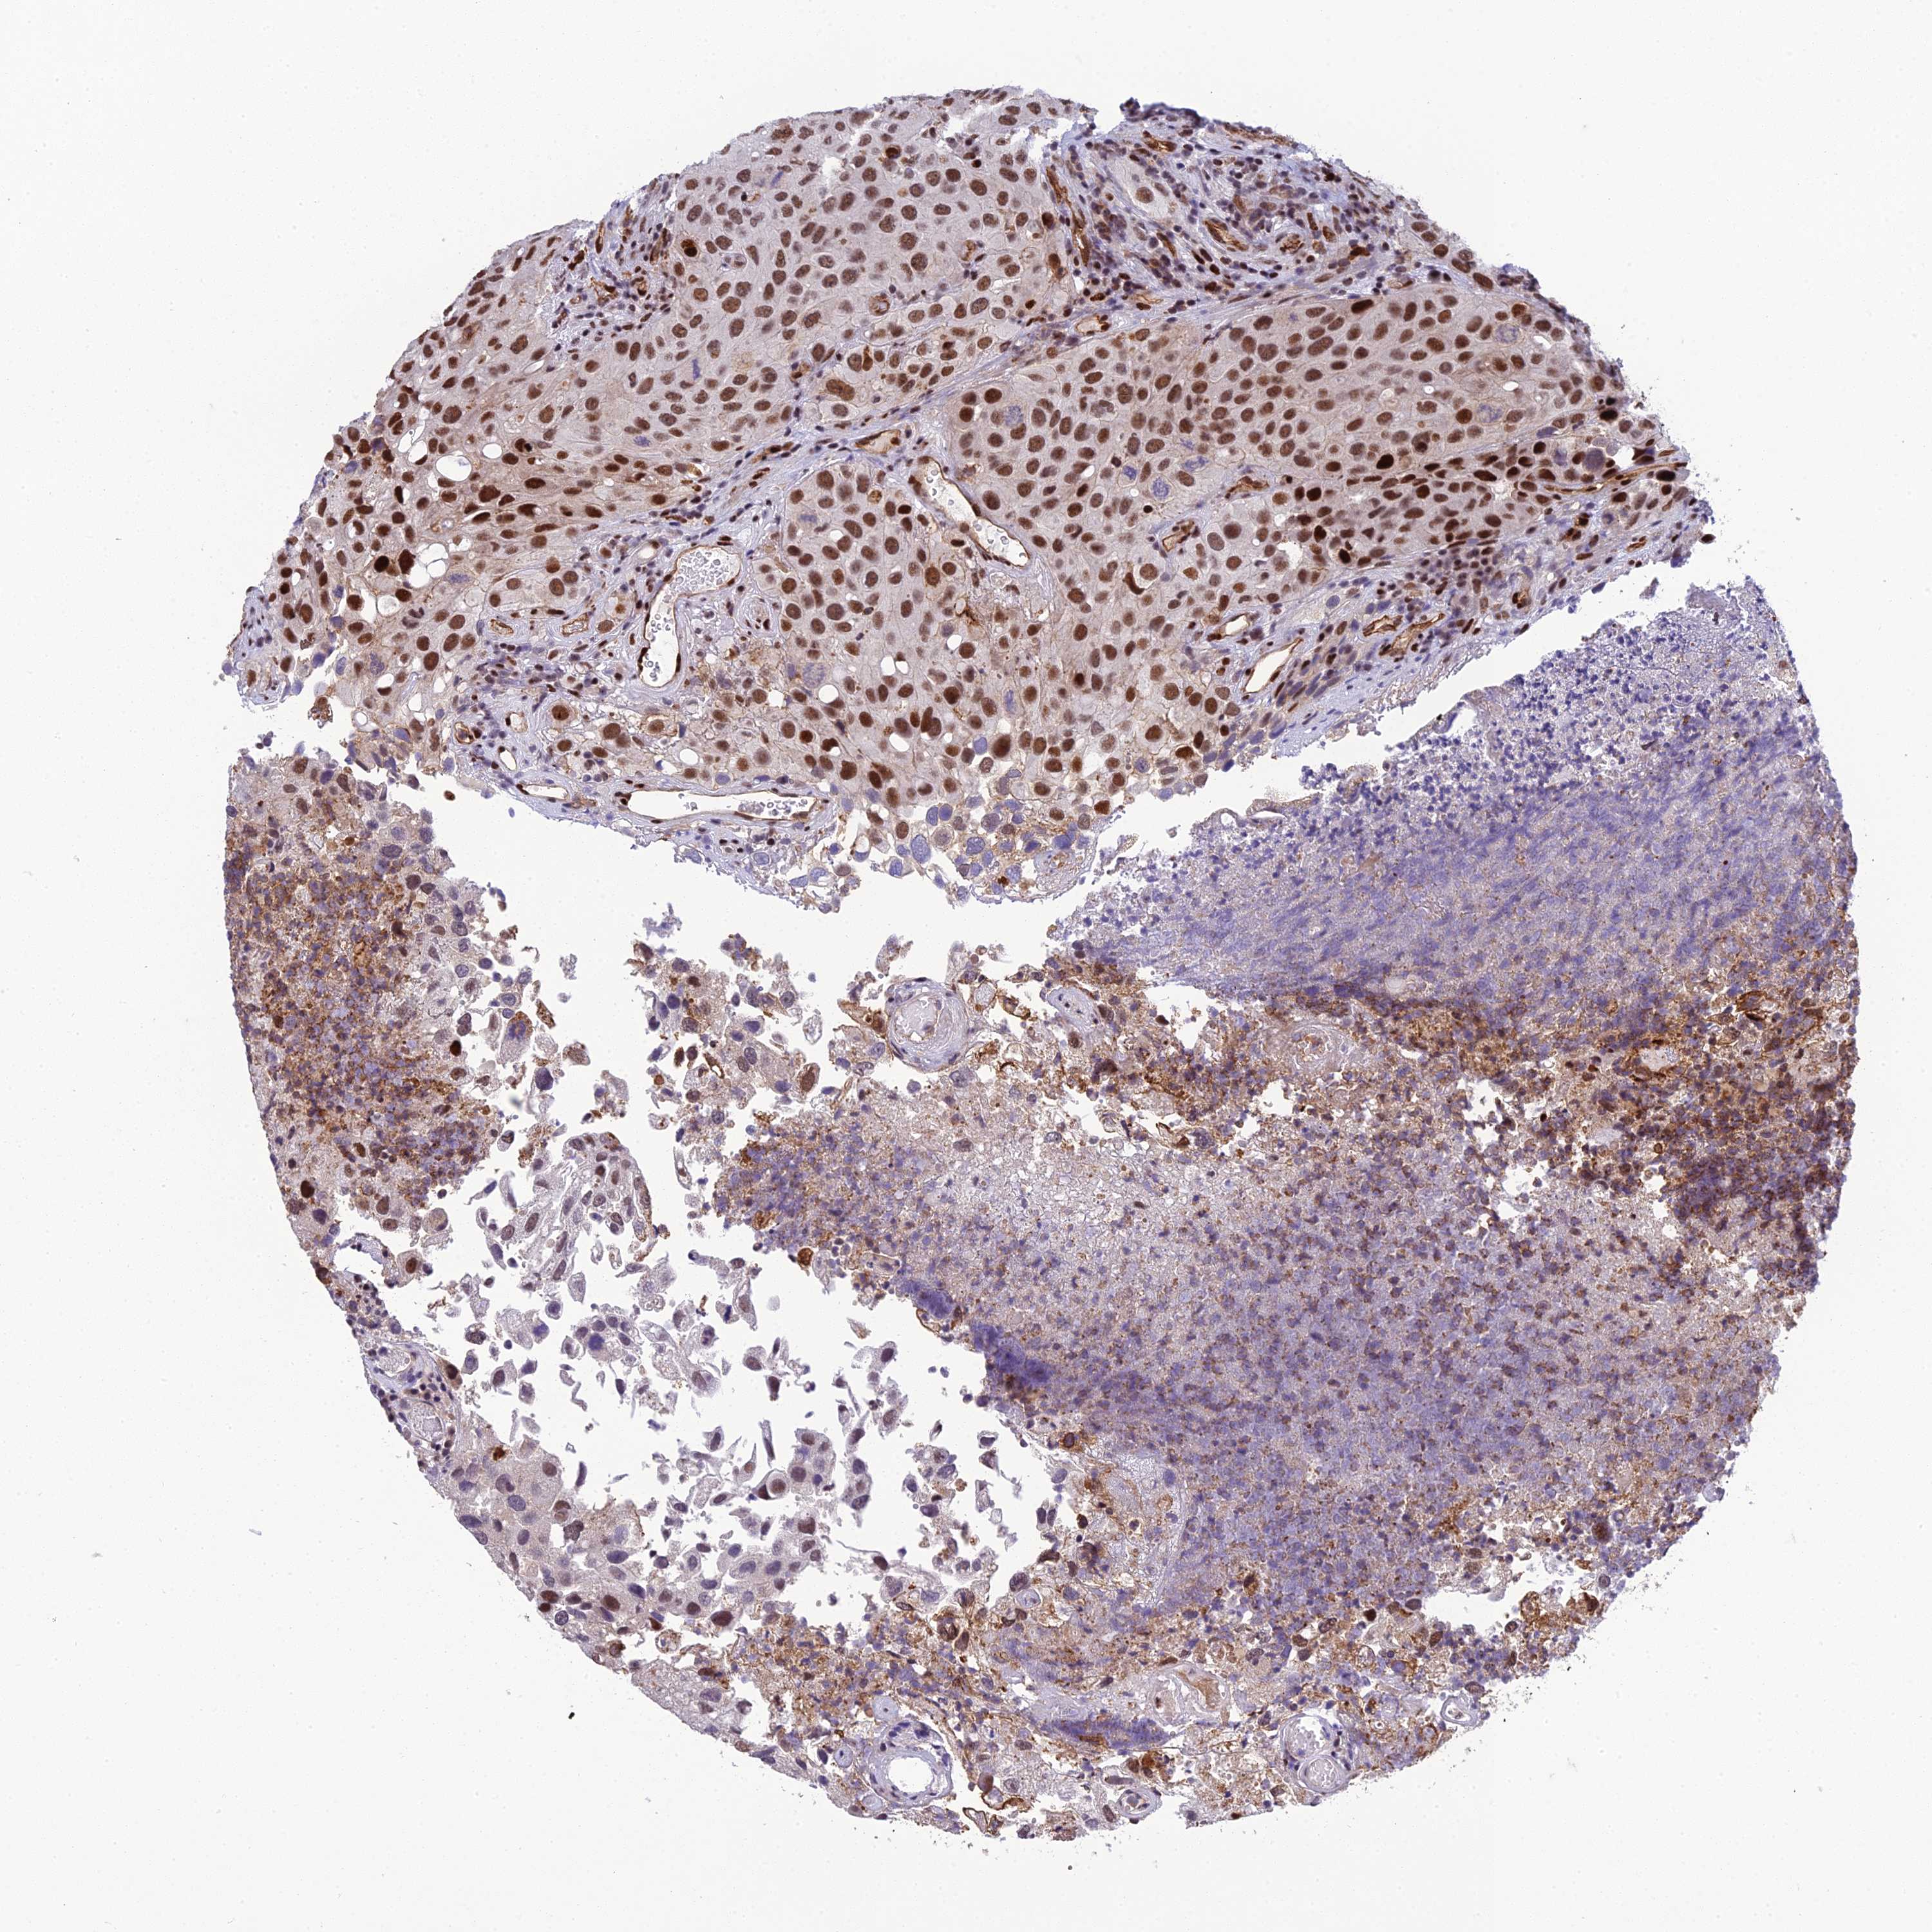

UROTHELIAL CANCER - Protein expressioni

A mouse-over function shows sample information and annotation data. Click on an image to view it in a full screen mode. Samples can be filtered based on level of antibody staining by selecting one or several of the following categories: high, medium, low and not detected. The assay and annotation is described here.

Note that samples used for immunohistochemistry by the Human Protein Atlas do not correspond to samples in the TCGA dataset.

Antibody stainingi

Antibody staining in the annotated cell types in the current human tissue is reported as not detected, low, medium, or high, based on conventional immunohistochemistry profiling in selected tissues. This score is based on the combination of the staining intensity and fraction of stained cells.

Each image is clickable and will lead to virtual microscopy that enables deeper exploration of all samples and also displays staining intensity scores, fraction scores and subcellular localization as well as patient and tissue information for each sample.

Antibody HPA043375

Antibody HPA043389

Staining

High

Medium

Low

Not detected

Intensity

Strong

Moderate

Weak

Negative

Quantity

>75%

75%-25%

<25%

None

Location

Nuclear

Cytoplasmic/membranous

Cytoplasmic/membranous,nuclear

Urothelial carcinoma, High grade

Urothelial carcinoma, Low grade